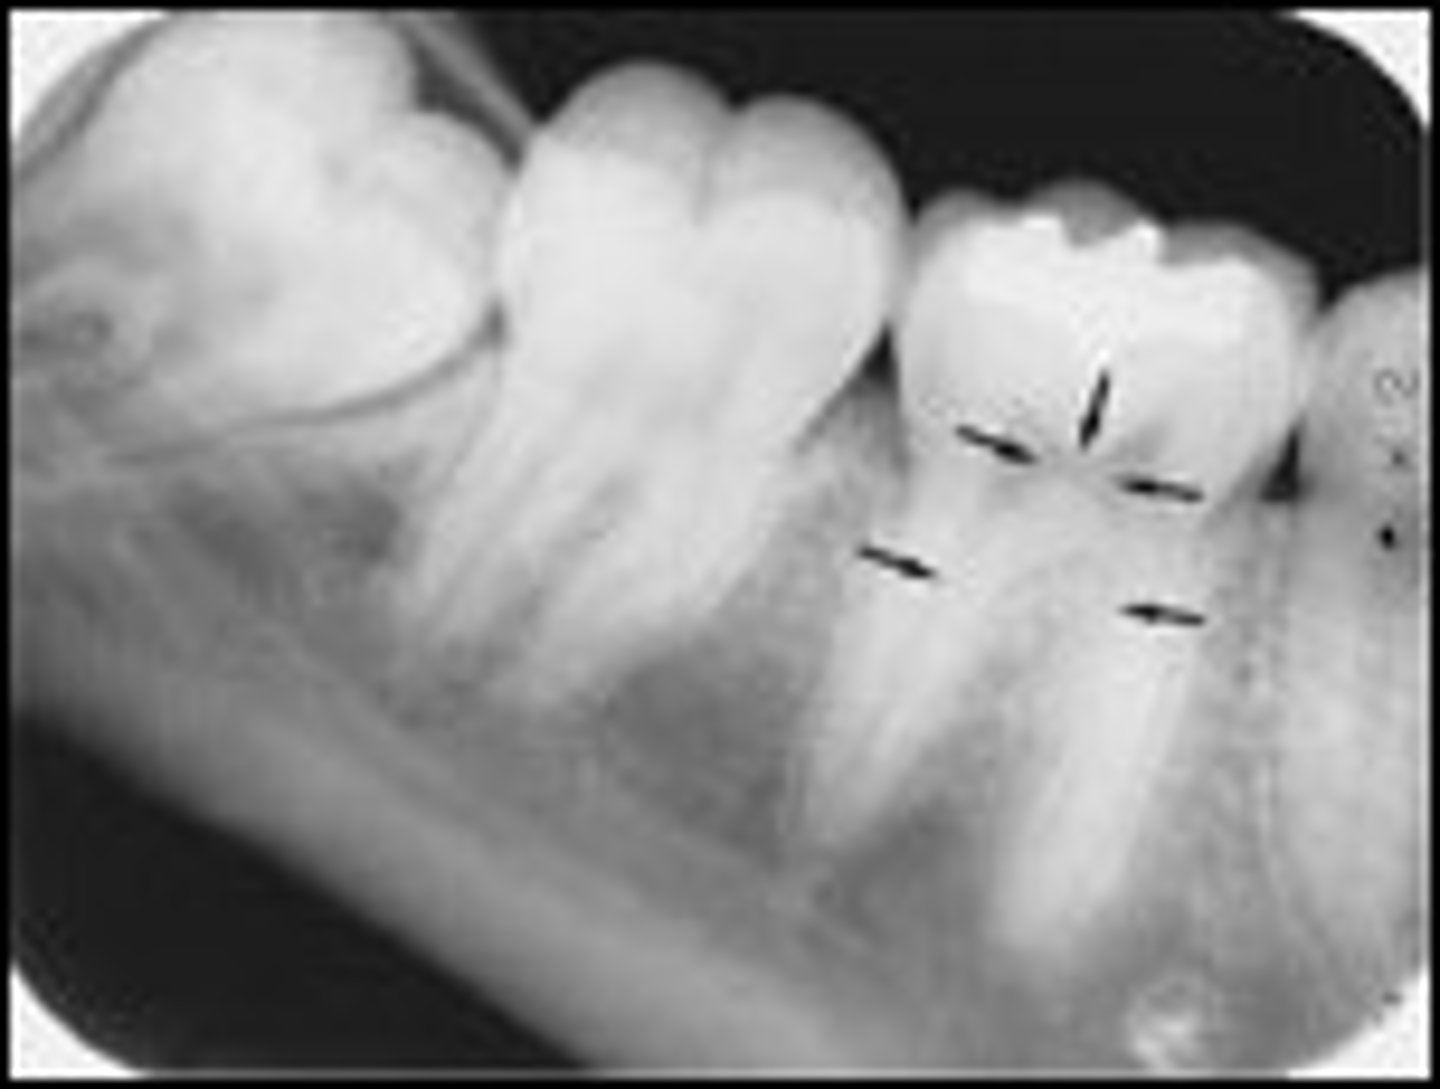

Cortical bone

What kind of bone is shown here?

Cancellous bone